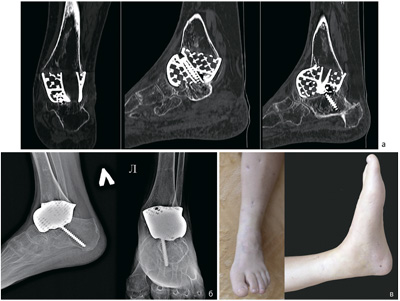

Replacement of Total and Subtotal Defects of the Calcaneus in Patients with Osteomyelitis Using Custom 3D Implants

Total and subtotal defects of the calcaneus constitute a complex and urgent problem in contemporary traumatology, without a definitive solution. Nevertheless, the treatment of patients presenting with defects secondary to distal neuropathy complicated by chronic infection remains an even more challenging clinical issue.